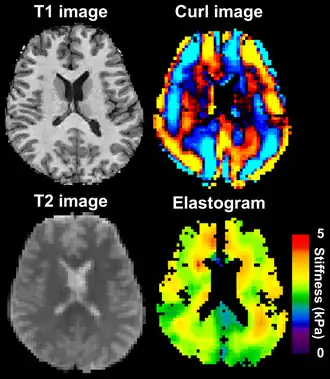

MRE is conducted in three steps: first, a mechanical vibrator is used on the surface of the patient's body to generate shear waves that travel into the patient's deeper tissues; second, an MRI acquisition sequence measures the propagation and velocity of the waves; and finally this information is processed by an inversion algorithm to quantitatively infer and map tissue stiffness in 3-D.[2][3] This stiffness map is called an elastogram, and is the final output of MRE, along with conventional 3-D MRI images as shown on the right.[2]

![]() Magnetic resonance elastography of the brain. A T1 weighted anatomical image is shown in the top-left, and the corresponding T2 weighted image from the MRE data is shown in the bottom-left. The wave image used to make the elastogram is shown in the top-right, and the resulting elastogram is in the bottom-right. | |

MRE of the brain [27] was first presented in the early 2000s.[28][29] Elastogram measures have been correlated with memory tasks,[30] fitness measures,[31] and progression of various neurodegenerative conditions.[27] For example, regional and global decreases in brain viscoelasticity have been observed in Alzheimer's disease[32][33] and multiple sclerosis.[34][35] It has been found that as the brain ages, it loses its viscoelastic integrity due to degeneration of neurons and oligodendrocytes.[36][37] A recent study looked into both the isotropic and anisotropic stiffness in brain and found a correlation between the two and with age, particularly in gray matter.[38]